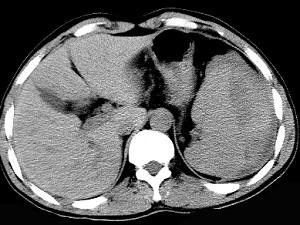

男、52岁1小时前车祸,伤及左季肋区,CT扫描如图,最可能的诊断是 ( )A、脾脓肿B、脾淋巴瘤C、脾破裂D、脾血管瘤E、脾梗死

问题 男、52岁1小时前车祸,伤及左季肋区,CT扫描如图,最可能的诊断是 ( )

选项 A、脾脓肿 B、脾淋巴瘤 C、脾破裂 D、脾血管瘤 E、脾梗死

答案 C